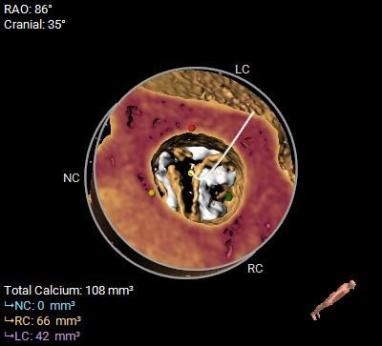

该病例主动脉根部结构较小,并且左冠脉开口高度距离瓣环较近,只有10.2mm,有一定的冠脉阻挡风险,手术团队讨论后决定在TAVR时进行冠脉保护,提前将冠脉通路准备好,并且结合球囊扩张及瓣膜释放工作位综合评估。

综合以上分析及病例特点,手术策略如下:三叶式主动脉瓣,轻度钙化伴瓣叶增厚,左冠开口较低,右冠高度可,综合瓦氏窦内径、窦管交界内径等因素考虑,左冠行冠脉保护,非横位心,弓距弓角可,左室内径可,双侧入路血管走形良好,整体入路血管条件可。计划使用20mm球囊预扩,预装23型号瓣膜,释放高度零位开始释放,最终依据术中情况决定是否做烟囱支架冠脉保护技术。

术中影像